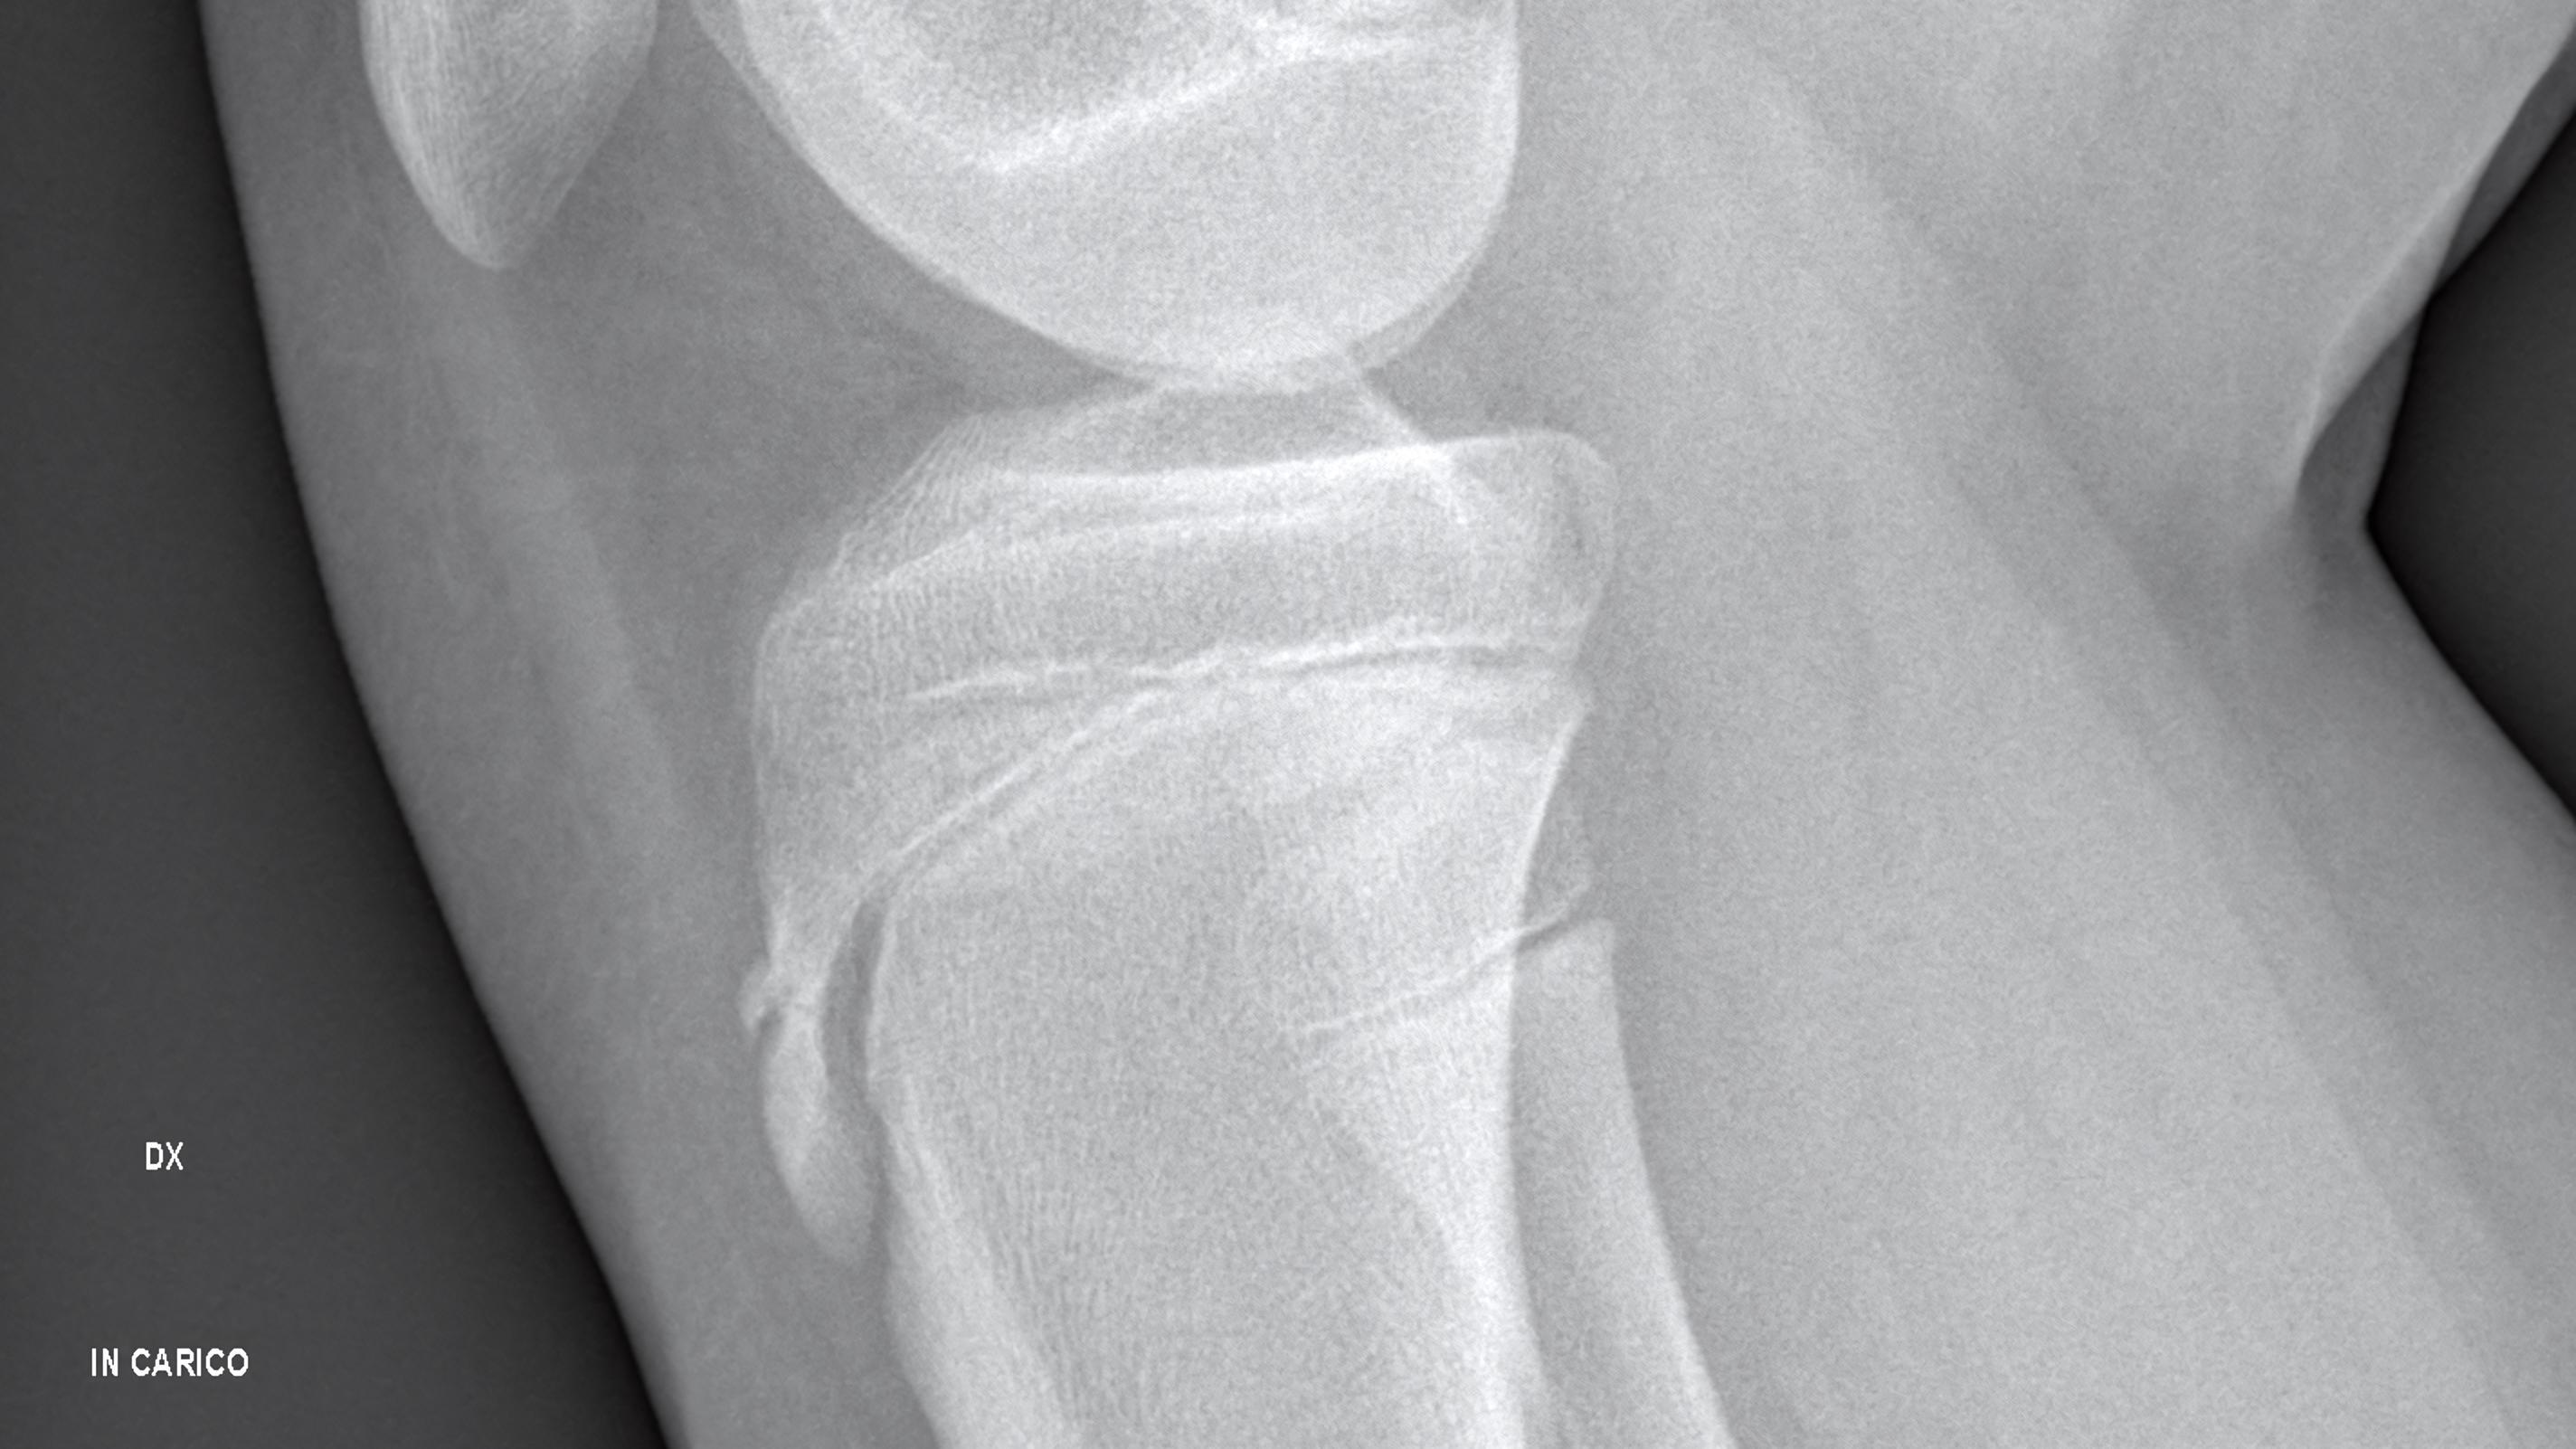

Osgood-Schlatter occurs when the patellar tendon (the tendon below your kneecap) pulls repeatedly on a growth area of the shinbone called the tibial tuberosity.

This leads to pain, inflammation, and sometimes a visible bump just below the kneecap.

A hard or bony bump under the knee